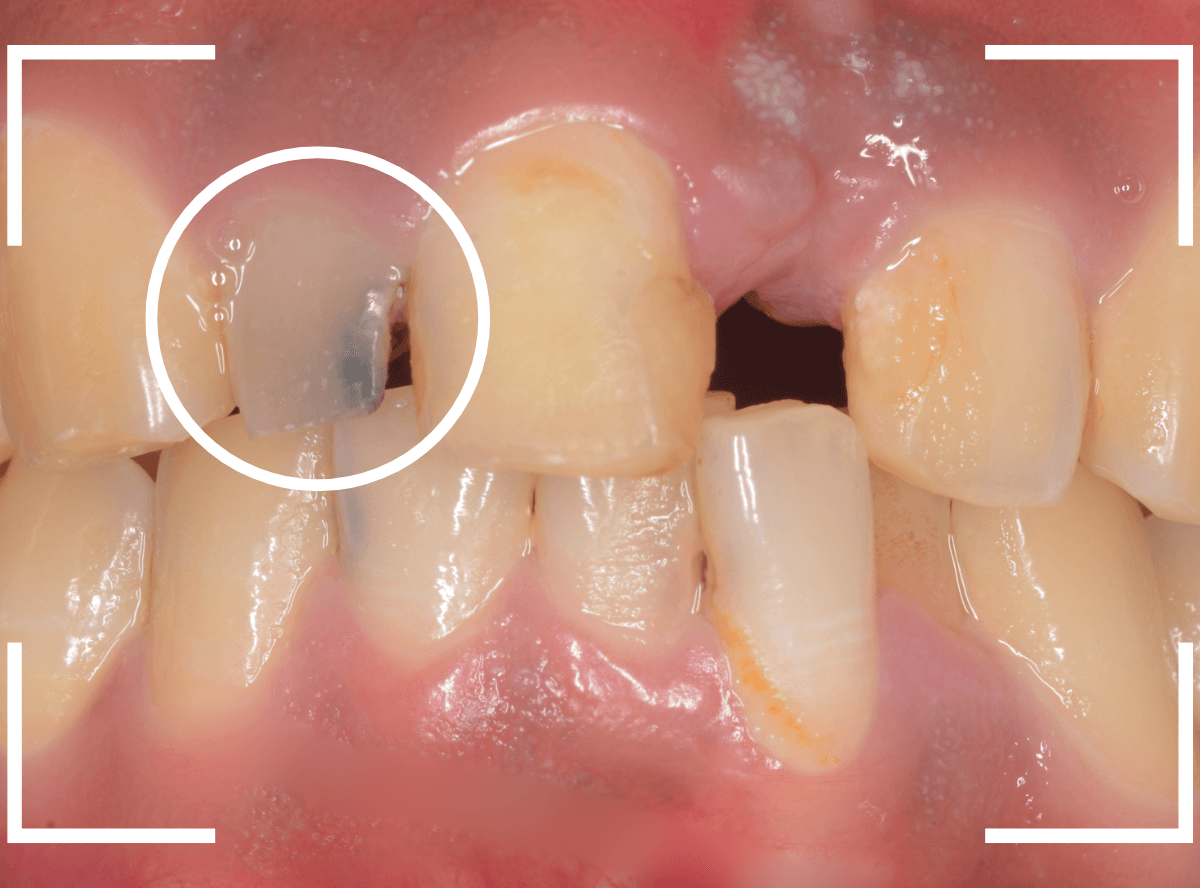

さし歯の中には大きなメタル・コアが入っています。。。

さし歯の周りの歯肉が若干黒ずんでるのも、これが原因でしょう。

せっかくさし歯をやり直すのであれば、このメタル・コアもやりなおしたいところです。

かなり怖かったですが、患者さんにも頑張っていただいて、さし歯を除去後、時間をかけて慎重にメタルコアを除去しました。

無事にメタルコアを除去できましたので、ファイバーコアに置き換えます。